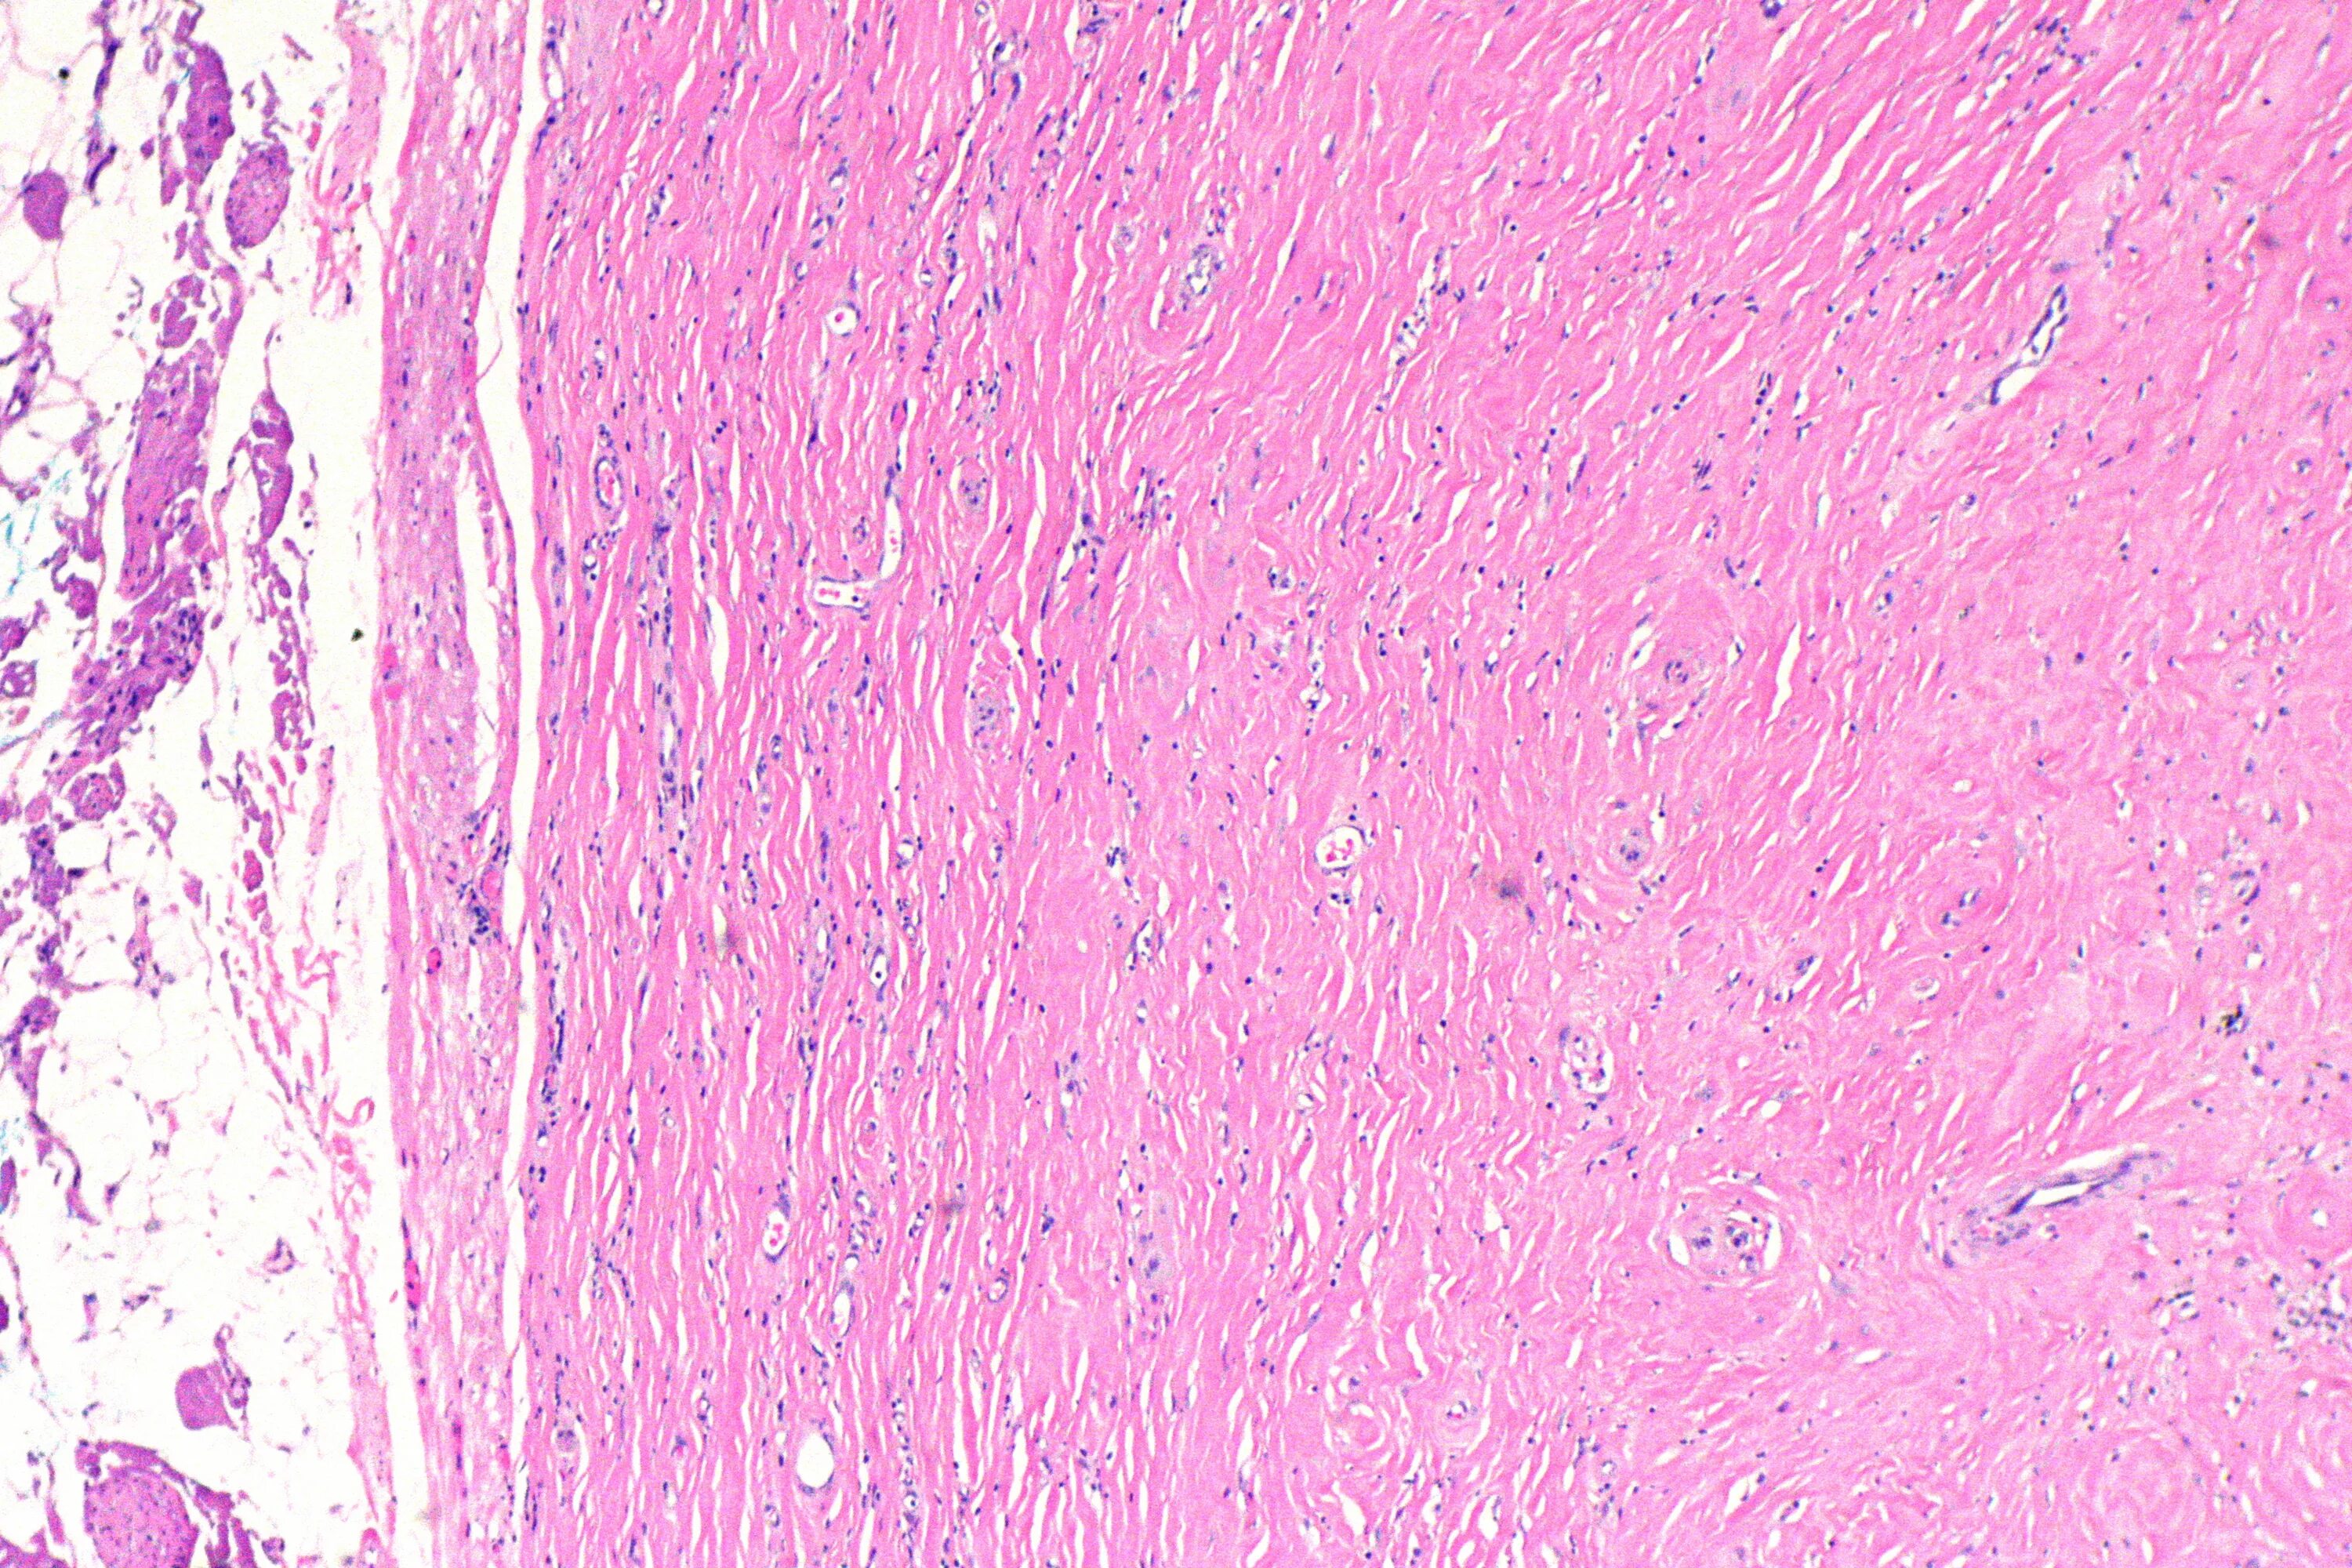

Миокард гистология